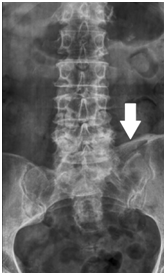

Figure 2 Anteroposterior lumbar spines X-Ray demonstrating the same ossification of the left iliolumbar ligament (white arrow).